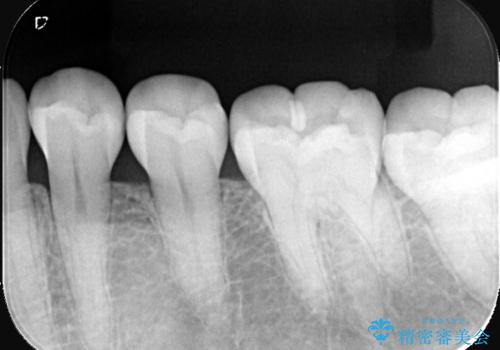

- 主訴:左下の奥歯がなんだか他の歯に比べて青白い気がする。虫歯じゃないか見てほしい。

左下6番目の歯の咬合面で虫歯が進行しており、プラスチックを用いた治療とセラミックを用いた治療を提案し、適合や材料安定性の良いセラミックインレーでのやり替えとなりました。

咬合面のカリエスの場合、CR修復で済ませることが多いですが、CRは経年的に劣化し二次う蝕を引き起こすリスクがあるため適合や経年劣化しにくいセラミックでの治療となりました。